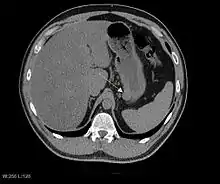

The purpose of radiologic imaging is to locate the lesion, evaluate for signs of invasion and detect metastasis. Features of GIST vary depending on tumor size and organ of origin. The diameter can range from a few millimeters to more than 30 cm. Larger tumors usually cause symptoms in contrast to those found incidentally which tend to be smaller and have better prognosis.[4][12] Large tumors tend to exhibit malignant behavior but small GISTs may also demonstrate clinically aggressive behavior.[13]

Preferred imaging modalities in the evaluation of GISTs are CT and MRI,[15]:20–21 and, in selected situations, endoscopic ultrasound. CT advantages include its ability to demonstrate evidence of nearby organ invasion, ascites, and metastases. The ability of MRI to produce images in multiple planes is helpful in determining the bowel as the organ of origin (which is difficult when the tumor is very large), facilitating diagnosis.

As the tumor grows it may project outside the bowel (exophytic growth) and/or inside the bowel (intraluminal growth), but they most commonly grow exophytically such that the bulk of the tumor projects into the abdominal cavity. If the tumor outstrips its blood supply, it can necrose internally, creating a central fluid-filled cavity with bleeding and cavitations that can eventually ulcerate and communicate into the lumen of the bowel. In that case, barium swallow may show an air, air-fluid levels or oral contrast media accumulation within these areas.[13][16] Mucosal ulcerations may also be present. In contrast enhanced CT images, large GISTs appear as heterogeneous masses due to areas of living tumor cells surrounding bleeding, necrosis or cysts, which is radiographically seen as a peripheral enhancement pattern with a low attenuation center.[12] In MRI studies, the degree of necrosis and bleeding affects the signal intensity pattern. Areas of bleeding within the tumor will vary its signal intensity depending on how long ago the bleeding occurred. The solid portions of the tumor are typically low signal intensity on T1-weighted images, are high signal intensity on T2-weighted images and enhance after administration of gadolinium. Signal-intensity voids are present if there is gas within areas of necrotic tumor.[14][17][18]

Malignancy is characterized by local invasion and metastases, usually to the liver, omentum and peritoneum. However, cases of metastases to bone, pleura, lungs and retroperitoneum have been seen. In distinction to gastric adenocarcinoma or gastric/small bowel lymphoma, malignant lymphadenopathy (swollen lymph nodes) is uncommon (<10%) and thus imaging usually shows absence of lymph node enlargement.[12] If metastases are not present, other radiologic features suggesting malignancy include: size (>5 cm), heterogeneous enhancement after contrast administration and ulcerations.[4][12][19] Also, overtly malignant behavior (in distinction to malignant potential of lesser degree) is less commonly seen in gastric tumors, with a ratio of behaviorally benign to overtly malignant of 3-5:1.[4] Even if radiographic malignant features are present, these findings may also represent other tumors and definitive diagnosis must be made immunochemically.